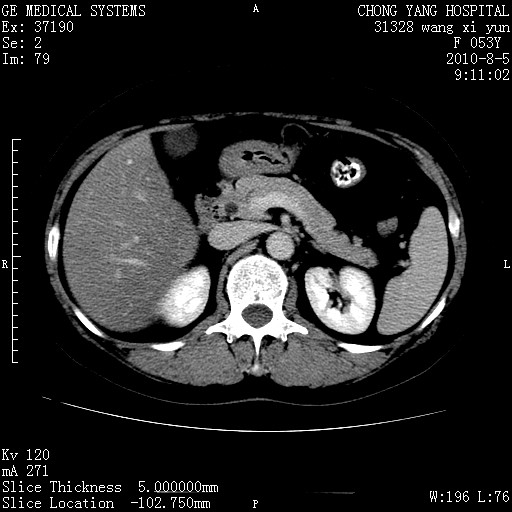

标题: CT28214:F41Y 血尿二十天,建议盆腔平扫加增强。

胆管细胞ca?

1)考虑肝左叶胆管细胞癌。2)脂肪肝。

支持胆管细胞ca。